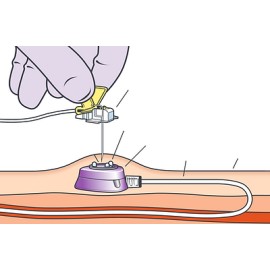

Eletrodo Meditrace 200 Adulto -Ag/AgCl - Gel Sólido (hidrogel) adesivo e condutor.

O Eletrodo Medi-Trace 200 é um eletrodo universal para a monitorização de adultos porque incorpora numerosas características para satisfazer as necessidades dos diversos departamentos.

O Gel Sólido adesivo-condutor consegue uma máxima adesão e contato elétrico, deixa menos resíduos e requer menos limpeza posterior.

Os eletrodos Medi-trace 200 superam as especificações da Associação para o Avanço de Instrumentos Médicos (AAMI) para eletrodos de monitorização e proporcionam uma excelente qualidade de traçado, com baixa impedância, o que facilita uma rápida estabilização da linha de base.